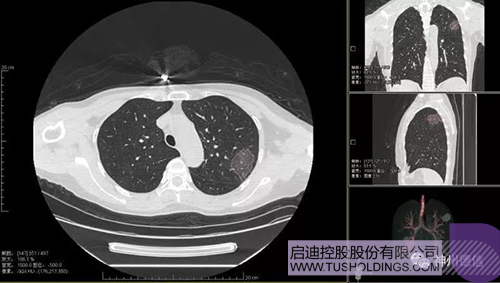

神州德信新冠肺炎檢測及智能量化分析系統(tǒng)

啟迪戰(zhàn)略投資企業(yè)神州德信作為國內(nèi)領先的肺部影像人工智能企業(yè),針對新型冠狀病毒肺炎開發(fā)了智能檢測及量化分析系統(tǒng),并在陜西、重慶等地定點醫(yī)院投入使用。該系統(tǒng)在疑似病例大規(guī)模快速篩查及精準診斷方面發(fā)揮了重要作用,特別是其具有的肺炎患者臨床影像跟蹤量化隨訪功能,為快速有效阻斷疫情擴散提供了有力武器。